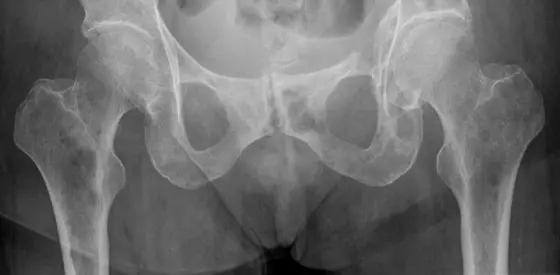

Mammakarzinom mit osteolytischen Metastasen